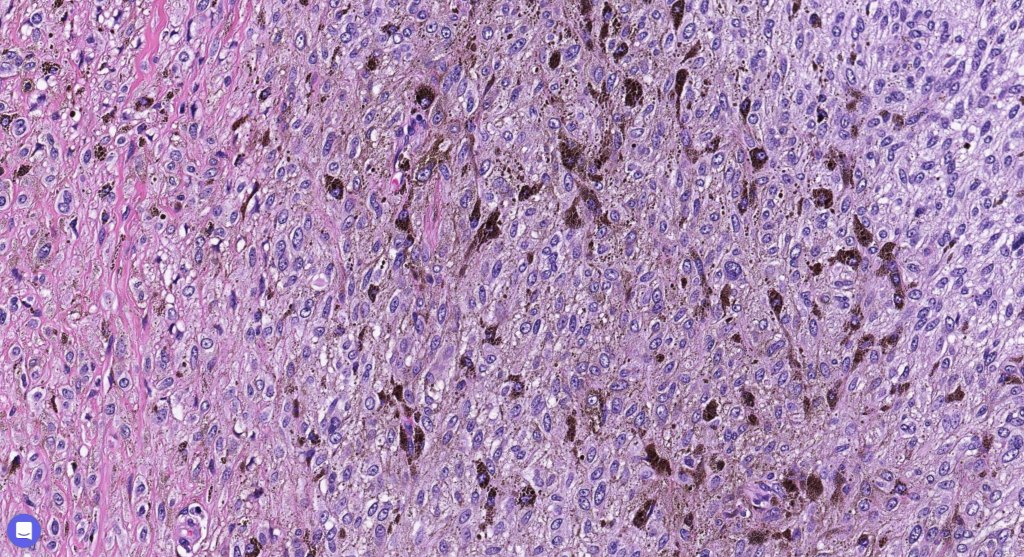

Histologically, it is characterized by a dense population of spindled, dendritic melnanocytes & melanophages with variable fibrosis. It may sometimes represent a component of a combined nevus. Mitotic activity is not usually present and pleomorphism is absent (see atypical blue nevus below). Involvement of the arrector pili muscle is not uncommon.

•Admixture of spindle cells, pigmented bipolar or dendritic cells & melanophages

•Cytoplasm is pale and nuclei are small with inconspicuous nucleoli

•Mitoses are typically very sparse or absent

•No atypical mitoses

•No Necrosis or lymphovascular invasion

•Some tumors are composed spindle cells in a fascicular or neuronevoid pattern

•Perineural involvement may be seen